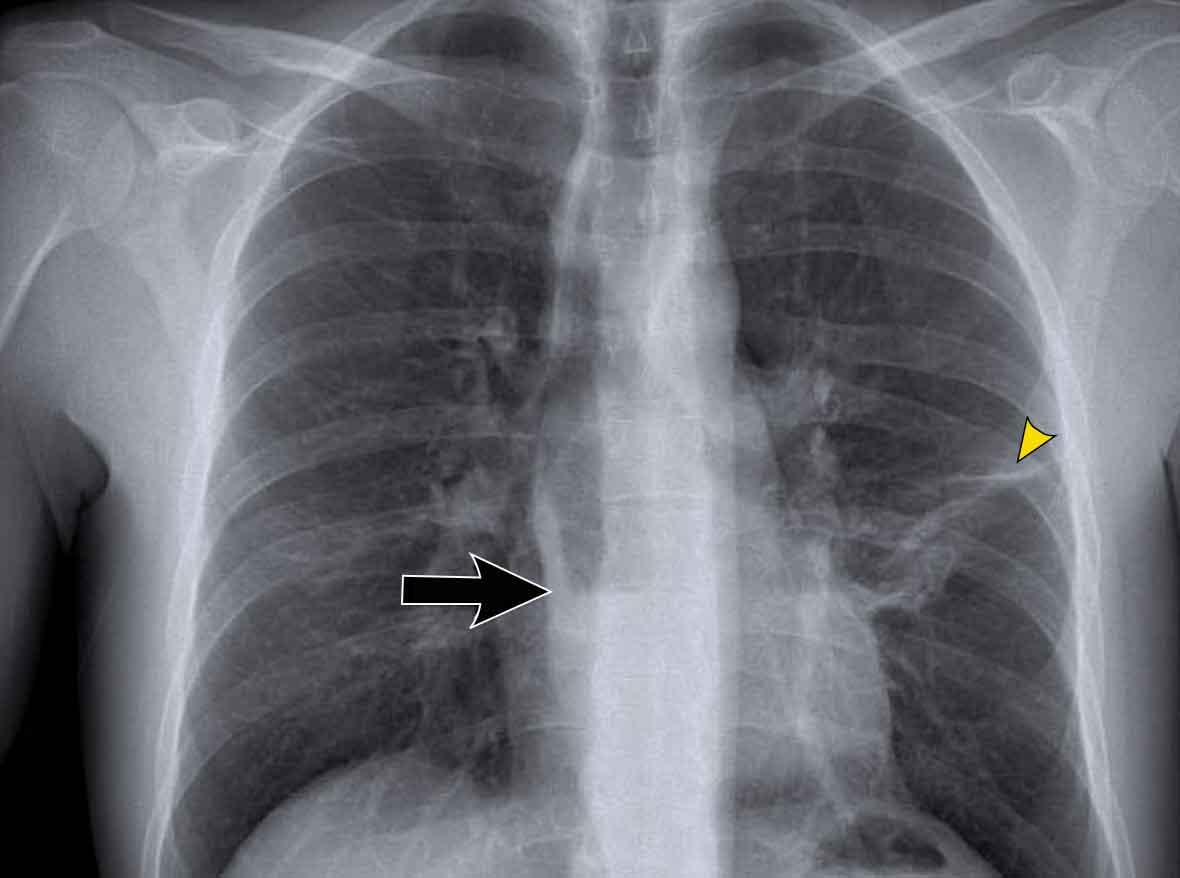

Dịch chuyển đường azygô-thực quản (1) – Thoát vị hoành

Thoát vị hoành (đầu mũi tên) là nguyên nhân phổ biến nhất gây dịch chuyển đường azygô-thực quản quan sát thấy trên phim tư thế thẳng (PA).

Lưu ý hình ảnh khí trong túi thoát vị trên phim tư thế nghiêng (mũi tên đen).

Dịch chuyển đường azygô-thực quản (3)

Trước tiên hãy phân tích phim X-quang ngực.

Sau đó tiếp tục đọc.

Dấu hiệu hình ảnh

- Dịch chuyển đường azygô-thực quản cả lên trên lẫn xuống dưới

- Hình ảnh mức khí-dịch, phù hợp với thực quản giãn chứa dịch

- Đám mờ quanh rốn phổi trái ở vùng lưỡi phổi, được cho là do viêm phổi hít trước đó

Chẩn đoán của bạn là gì?

Tiếp tục với phim X-quang ngực cũ và CT…

Phim X-quang ngực cũ:

- Tư thế AP cho thấy khối cạnh khí quản phải

- Ngách azygô-thực quản không quan sát được; bị đẩy lệch và chạy song song với bờ nhĩ phải

- Đám mờ hình tròn lớn ở phổi trái phù hợp với viêm phổi hít

Hình ảnh CT:

- Thực quản giãn rõ rệt

- Không có bằng chứng về khối gây tắc nghẽn tại chỗ nối dạ dày-thực quản

- Chẩn đoán: Achalasia (co thắt tâm vị)